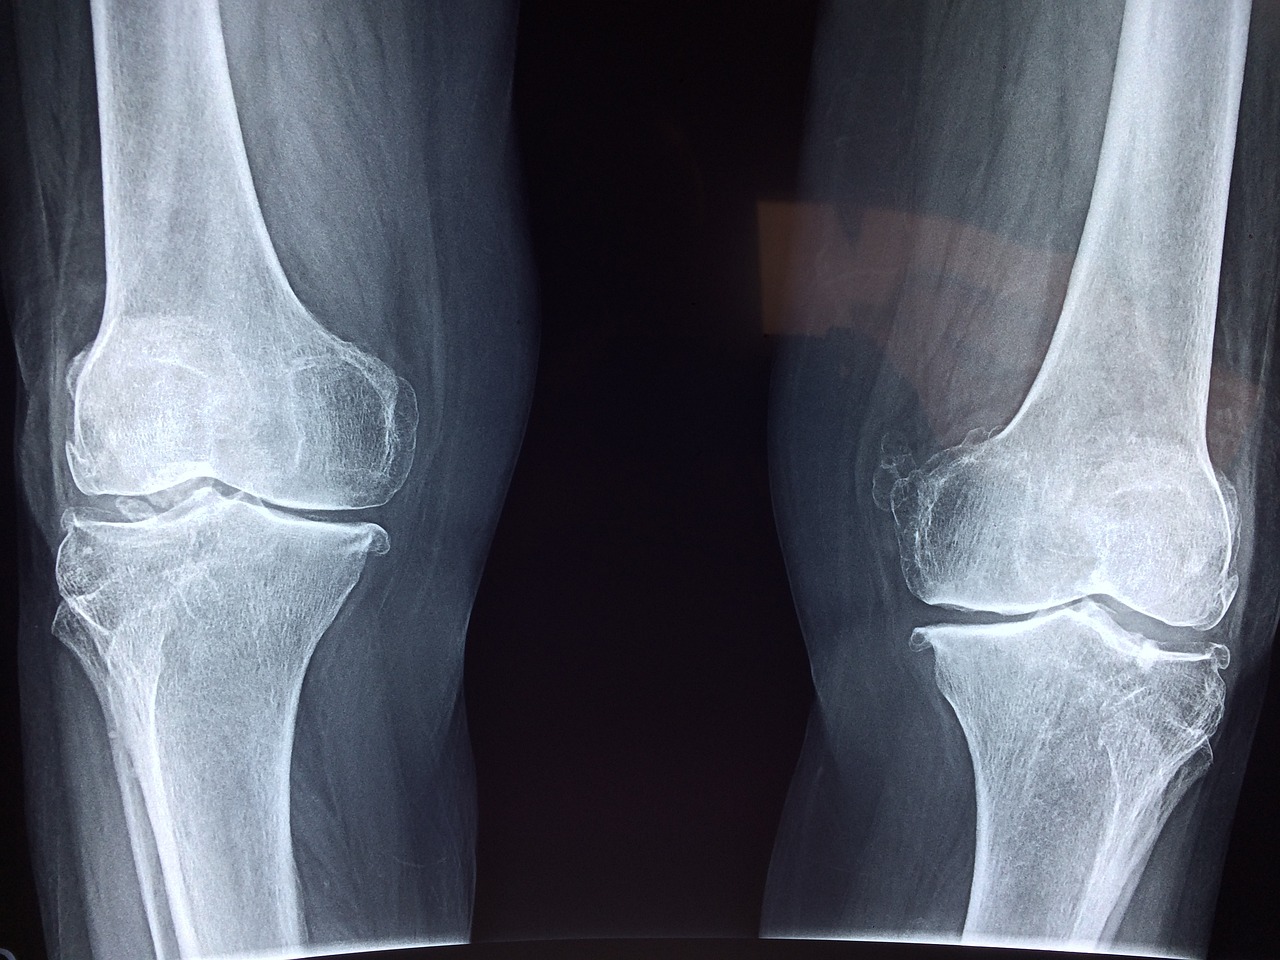

5. Osteoporosis Risk

One of the most well-known consequences of chronic calcium deficiency is an increased risk of osteoporosis. Without enough calcium, bones can become weak and porous, making them more prone to fractures.

7. Poor Bone Density

Low bone density, often detected through a bone density scan, can indicate calcium deficiency. Without sufficient calcium, your body may not build and maintain bone mass effectively, leading to weaker bones over time.